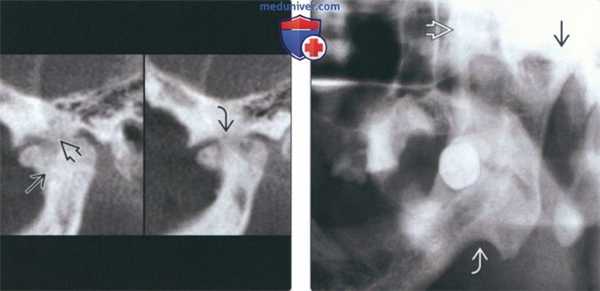

(Слева) На панорамной рентгенограмме у пациента с двухлоронним передним вывихом визуализируется правый мыщелок, смещенный кпереди и кверху относительно сулавного возвышения. Обратите внимание на явный передний открытый прикус, в то время как моляры находятся в окклюзии.

(Справа) На панорамной рентгенограмме у этого же пациента определяются аналогичные изменения слева. Открытый прикус обусловлен неправильным передним положением мыщелка, контакт задних зубов - его верхним положением.